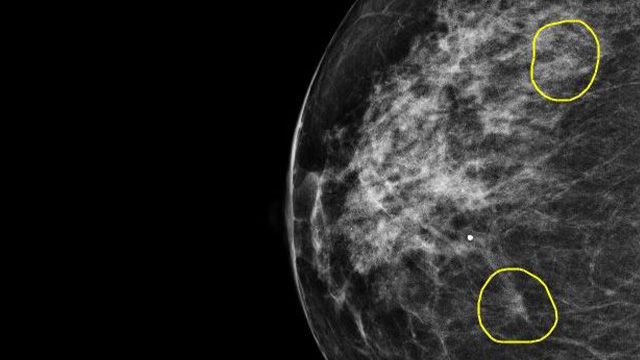

Enhancing healthcare with AI innovation

Discover how AI is improving breast cancer detection in the UK, helping doctors detect 12% more cases and potentially saving 30% of workload. This breakthrough marks a major step forward in the healthcare sector.